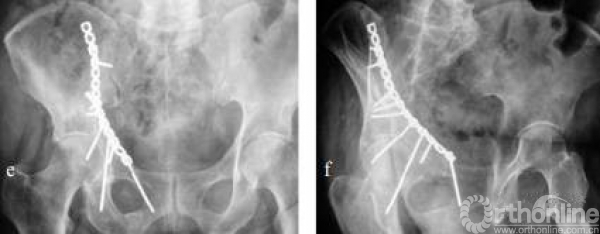

后柱螺钉的方向与角度

最难螺钉:前后柱螺钉,可连接髋臼的前柱和后柱。该螺钉十分困难,但如果固定,则十分有效。

从髂耻隆起处,水平向后柱进针,直达后柱。

该螺钉通道十分狭窄,十分容易进入关节,为髋臼困难螺钉之一。